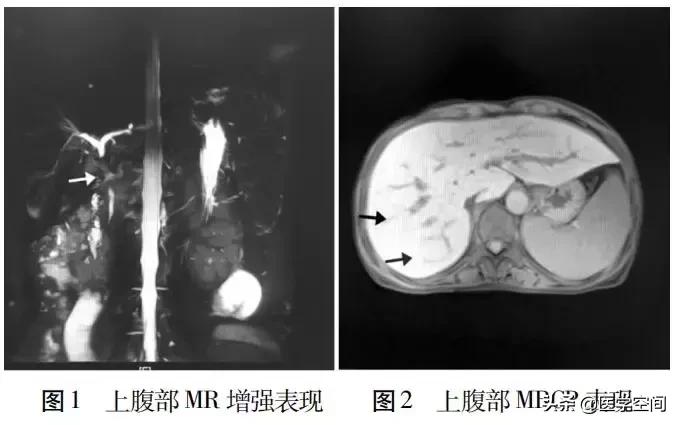

患者,女,49岁,身高151 cm,体质量42.3 kg,既往无乙肝病史。父亲曾有乙肝、黄疸病史,因肝癌去世,其弟弟亦有乙肝及黄疸病史。2017年7月无明显诱因下逐渐身体消瘦(体质量降低2.5 kg),后出现身目黄染,伴有小便黄,呈浓茶样,陶土样大便,量少,纳差,上腹部胀闷不适,白行服用胃药(具体不详)后无缓解。2018年2月10日身目黄染加重,门诊筛查肝炎分型均阴性,进一步行腹部CT增强扫描示:肝S4段小囊肿;肝右叶小斑点状钙化灶;肝门区淋巴管轻度扩张;胆囊结石。进一步行上腹部MR示:(1)早期肝硬化,脾大,胃底静脉曲张;肝内多发囊肿;胆囊未见显示,肝S4段小囊肿可能(图1);(2)磁共振胰胆管造影( MRCP)示胆总管胰上端未见显影,意义待查;(3)胆总管胰腺上段管壁疑增厚。于2月11日住院治疗,查自身免疫性肝病( AIH)示:SSA/52KD抗体阳性,抗gb210抗体阳性,抗线粒体M2抗体阳性;免疫全套示:免疫球蛋白A 4.29g/L,免疫球蛋白G 28 g/L,免疫球蛋白M 5.25 g/L;肝穿刺病理提示:肝细胞水肿,点状坏死及碎片状坏死,汇管区较多淋巴细胞浸润,胆管淤积,伴早期肝硬化形成,符合病毒性肝炎或者自身免疫性肝炎改变。免疫组化及特殊染色结果:Glypican-3(-),Hepatocyte(+),CD34血管(+),CK19(胆管+),Ki-67(散在+),p53(-),CEA(-),CDIO(-),PAS(-)。诊断为重叠综合征:AIH+原发性胆汁性肝硬化(PBC)。因护肝治疗后肝功能好转不明显,3月初行内窥镜下逆行胆管造影术( ER-CP)+鼻胆管引流,引流2周后黄疸症状减轻不明显,进一步行鼻胆管造影显示:胆总管无扩张,肝内胆管稀疏、僵直;胆管造影考虑:硬化性胆管。出院后坚持熊去氧胆酸( UDCA)250 mg、甘草酸二胺口服,每日3次。治疗后门诊复查肝功能提示:胆红素进行性升高(由122升至153 μmol/L),凝血功能均正常。7月21日复查上腹部MRCP:肝内胆管走行正常,轻度扩张,肝总管及胆总管上段显影不清,胆囊未见明确显影,胰管显影良好,未见明显扩张(图2)。胃镜提示:胃内多发溃疡,未予激素治疗,维持甘草酸二胺及熊去氧胆酸治疗。7月22日复查总胆红素上升至158 μmol/L.结合MRCP结果,以及患者长期陶土样大便,考虑为三重综合征:AIH+ PBC+原发性硬化性胆管炎( PSC)。以PSC为主,调整熊去氧胆酸250 mg,每日4次。7月31日复查肝功能较前好转,总胆红素下降至128.1 μmol/L,后病情稳定出院,1个月后黄疸较前进一步消退,患者自诉无特殊不适。